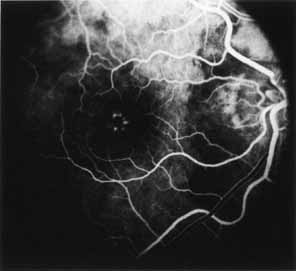

Ancillary Tests

Fluorescein angiography demonstrates increased transmission of choroidal fluorescence in the macula during early phases of the study, without late leakage of dye or fluorescein staining. In addition, an annular pattern of hyperfluorescence is often seen in the macula, highlighting the bull's-eye pattern seen on fundus examination (Fig. 4). Visual field defects include central scotoma, peripheral field loss, and ring scotoma.